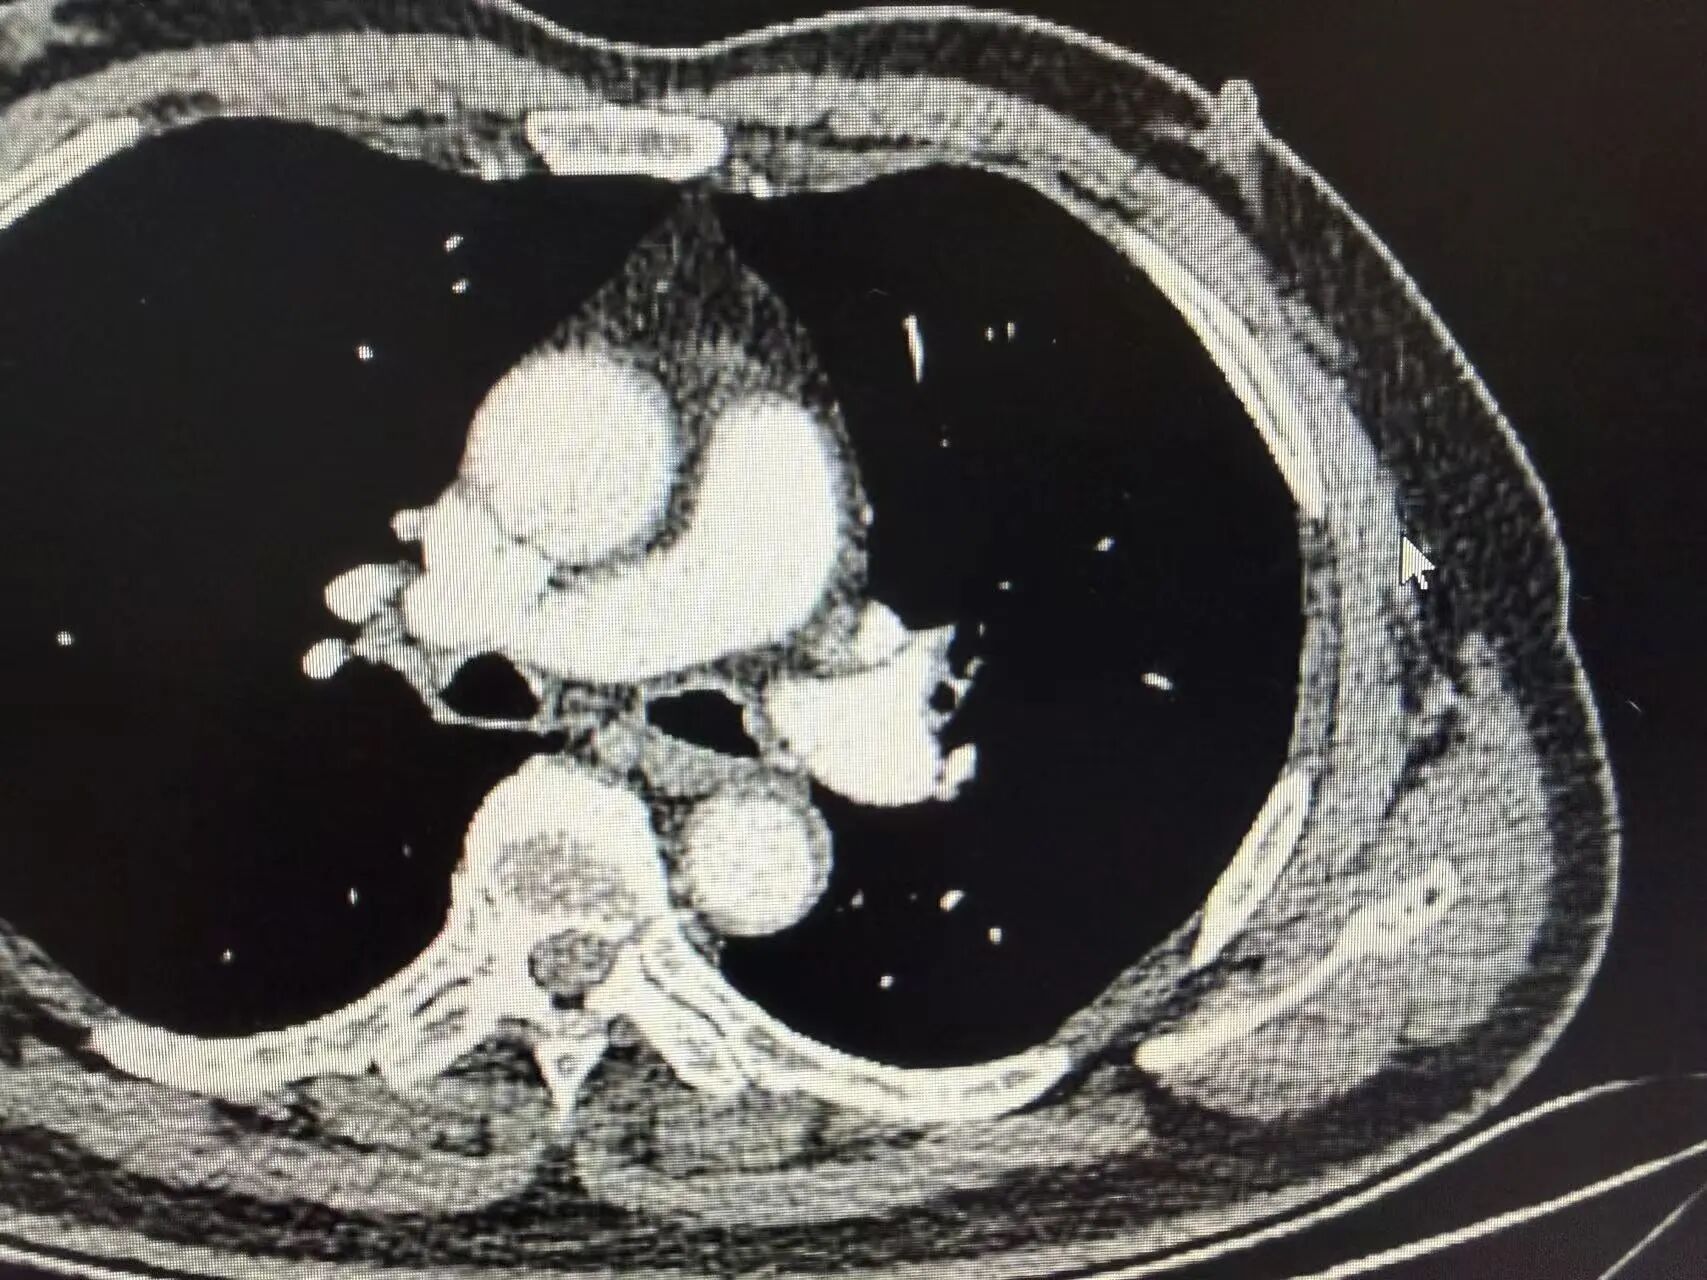

复查胸部CT显示:原左上肺肿瘤病灶显著缩小,肿大的肺门淋巴结基本恢复正常大小,肿瘤评估达到显著临床缓解,手术时机成熟。

新辅助治疗后CT影像